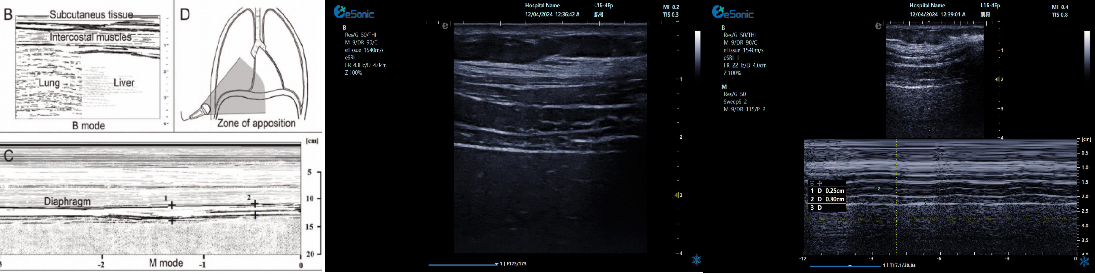

膈肌厚度检查

image.png

探头:高频线阵探头

部位:放置于腋前线与腋中线,7/8肋间或8/9肋间,沿肋间隙放置,观察和测量膈肌的厚度。

功能:M型超声,膈肌测量包

膈肌厚度变化

膈肌厚度测量

呼气末膈肌厚度正常值为2.0-3.5cm

膈肌活动度检查

探头:低频探头

部位:放置在腋前线或锁骨中线与肋缘交界处,启用M模式取样线垂直于膈肌,观察和测量膈肌运动幅度。

功能:M超,膈肌测量包

膈肌活动度测量